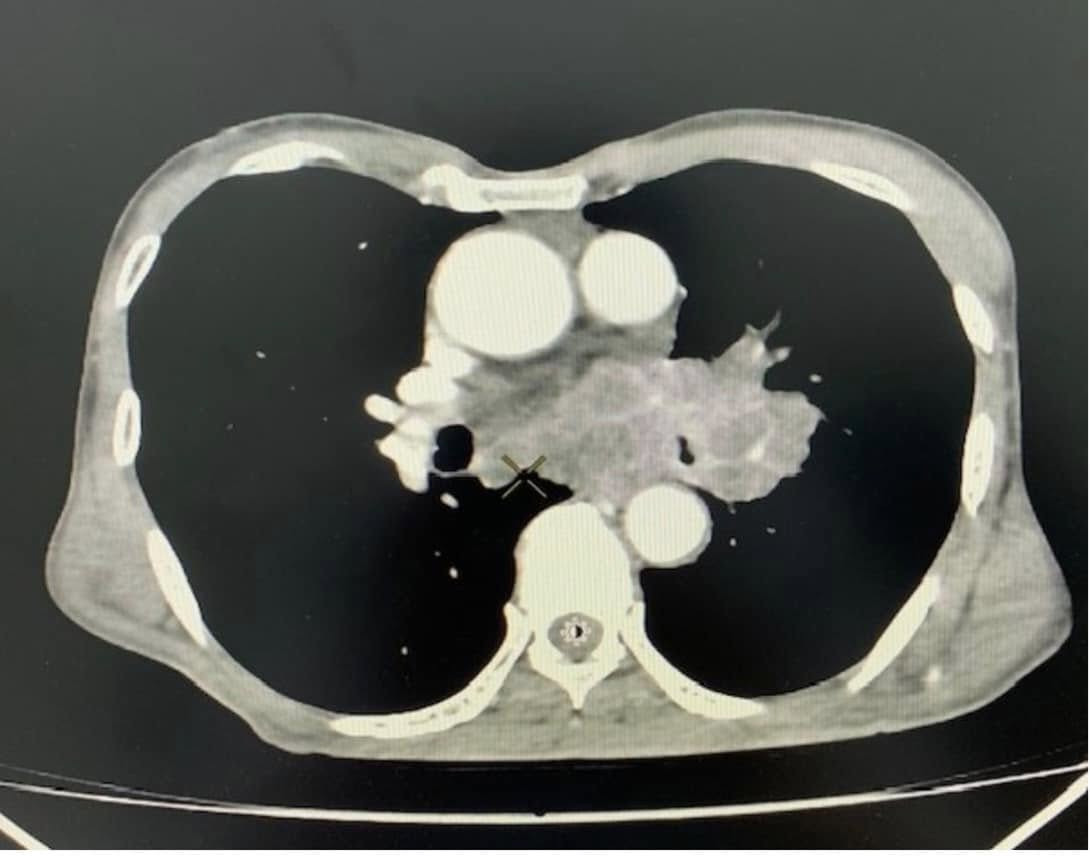

Kết quả chụp cắt lớp vi tính lồng ngực cho thấy bệnh nhân có khối u vùng trung thất và rốn phổi trái, bờ không đều, ngấm thuốc ở thành khối và vào các vách bên trong. Tổn thương hướng tới u phổi, dạng u phế quản trung tâm, xâm lấn trung thất, gây hẹp phế quản gốc trái. Sau khi có kết quả, ông N. đã được chuyển đến bệnh viện chuyên khoa để điều trị tiếp.